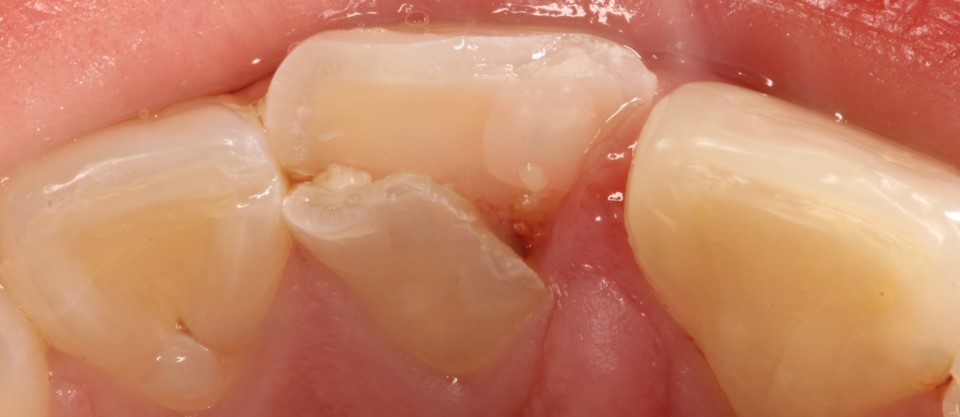

Внутриротовые фотографии 17.10.2022г

- б) Постоянные : 2.1 зуб

- Перелом 2.1 коронки зуба с повреждением пульпы зуба- S02.52